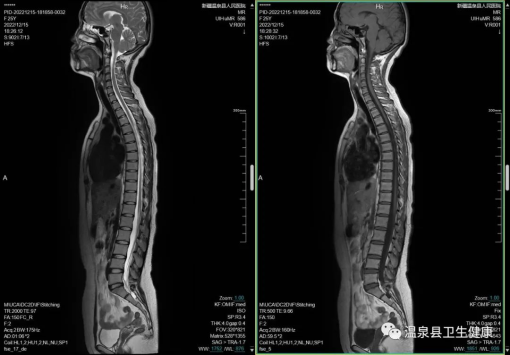

脊柱:椎间盘疾病,神经源性肿瘤,脊膜占位。

项目:腰椎MRI、胸椎MRI、颈椎MRI,MRM。